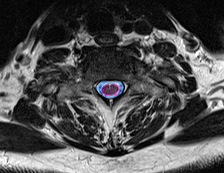

Φυσιολογικός ευρύς σπονδυλικός σωλήνας χωρίς πίεση στο νωτιαίο μυελό (κόκκινο περίγραμμα. |